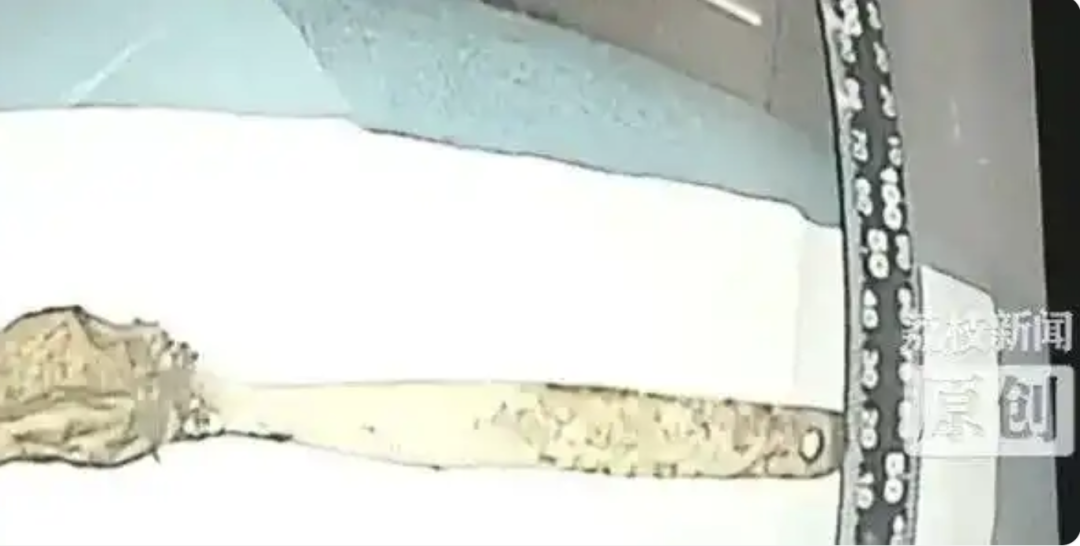

最后,周教授换回更牢固的“套圈”工具,稳稳套住勺柄,最终顺着食道,成功将这把15厘米长的陶瓷勺子完整地取了出来!

终被完整取出